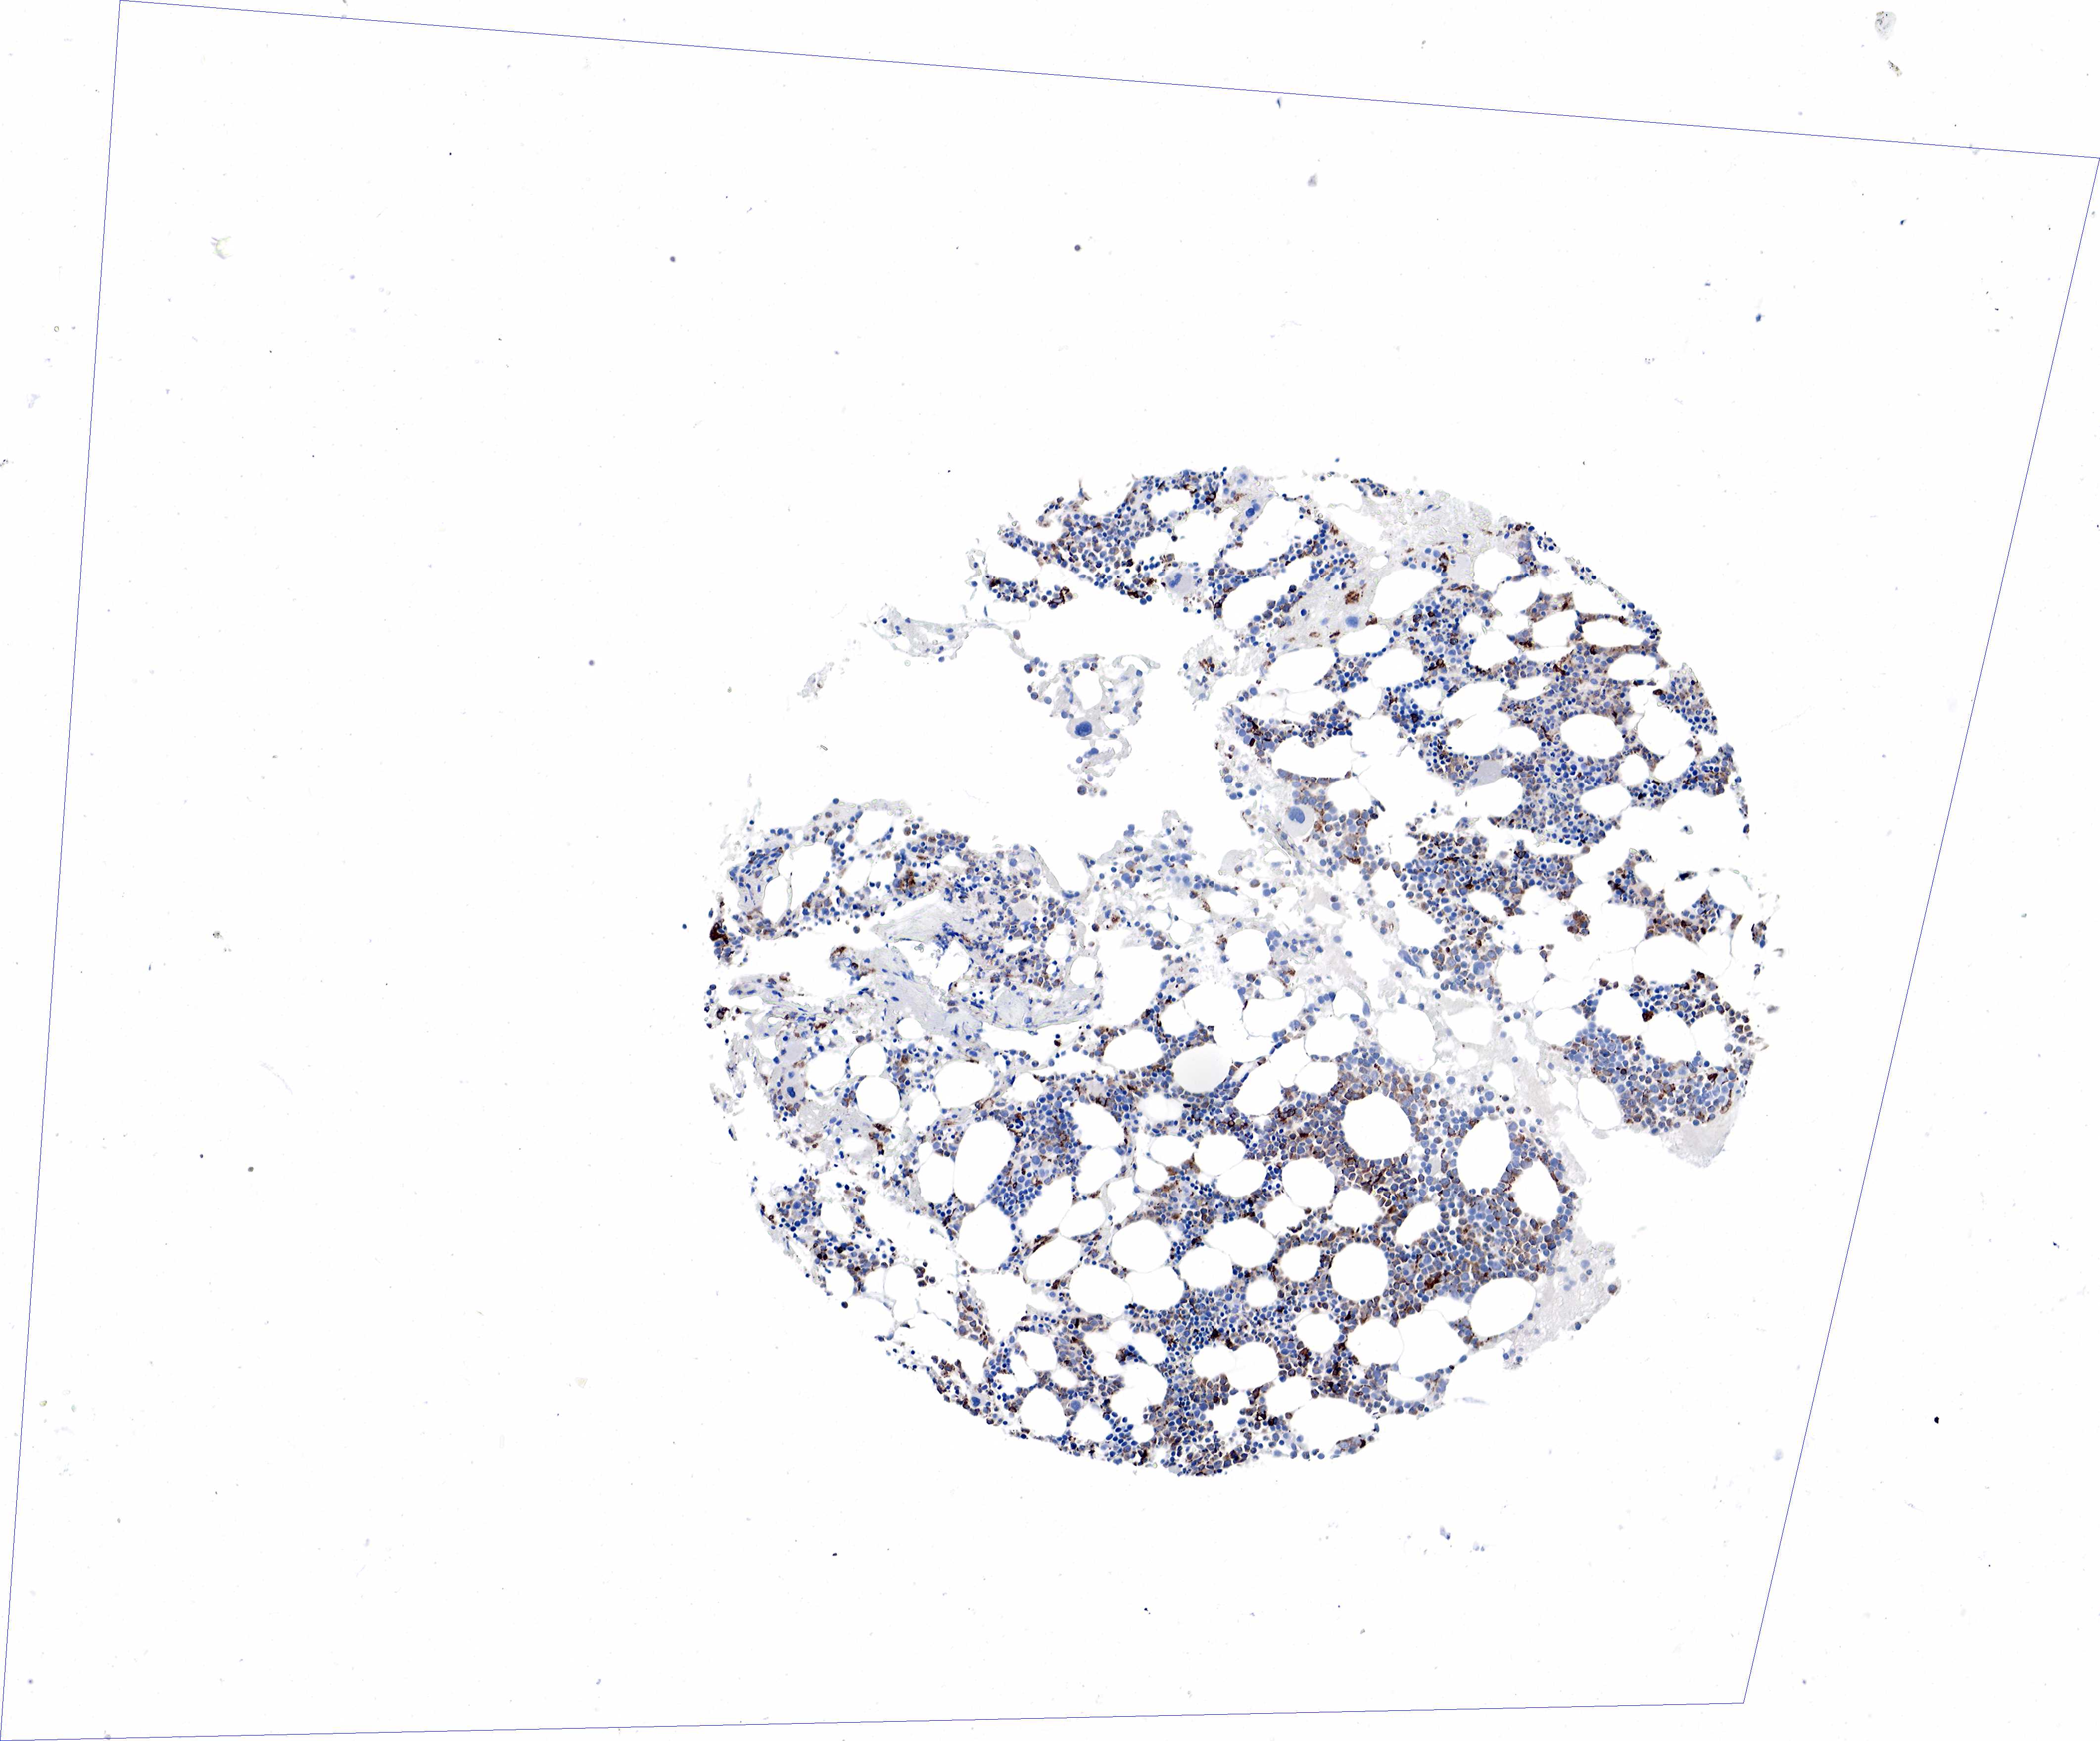

TISSUE PRIMARY DATA BONE MARROW Show tissue menu

BONE MARROW - Antibody stainingi

Antibody staining in the annotated cell types in the current human tissue is reported as not detected, low, medium, or high, based on conventional immunohistochemistry profiling in selected tissues. This score is based on the combination of the staining intensity and fraction of stained cells.

Each image is clickable and will lead to virtual microscopy that enables deeper exploration of all samples and also displays staining intensity scores, fraction scores and subcellular localization as well as patient and tissue information for each sample.

Antibody HPA048982Antibody CAB000051Antibody CAB000066Antibody CAB072861Antibody CAB072862

Hematopoietic cells MediumMediumMediumMediumHigh